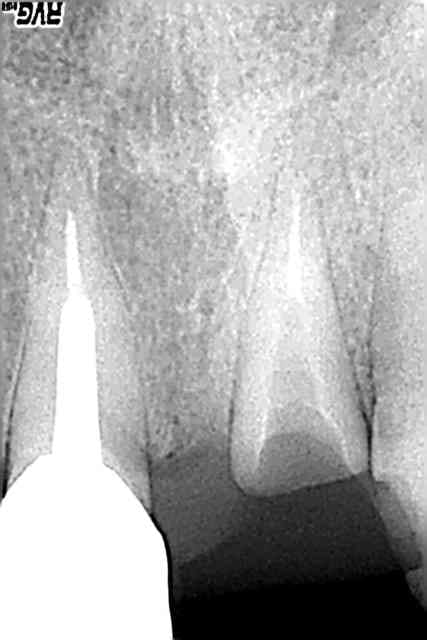

Rx.

c’est remarquable comment, même sans pression des forces mésialantes, les Inc. Inf. peuvent se mettre en rotation

@+ Bjc.